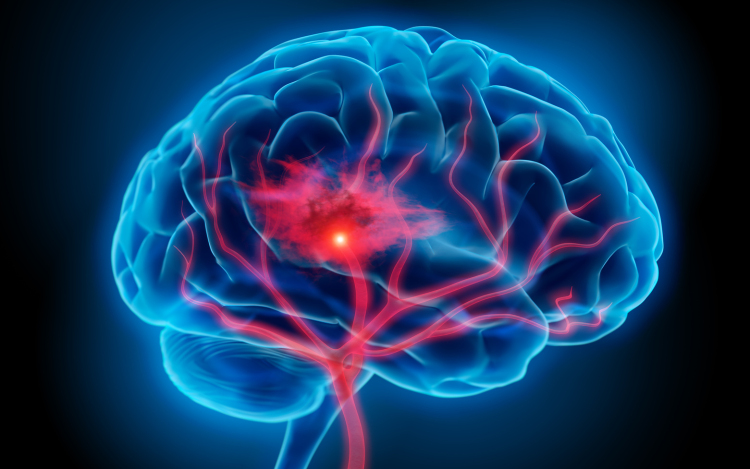

Óránként egy halálesetért a stroke felelős

Magyarországon évente 45 ezren kerülnek kórházba stroke miatt, óránként egy halálesetért felelős a betegség - mondta Bereczki Dániel, a Magyar Stroke Társaság elnöke az M1 aktuális csatornán szombat este.

Hozzátette, ma már tízezer alatt van azoknak a száma, akik belehalnak a stroke-ba, ami jelentős csökkenés 1980-hoz képest, amikor évente mintegy 24 ezren haltak meg ebben a betegségben.

Mint mondta, ennek oka, hogy az emberek egyre komolyabban veszik a kockázati tényezőket, elsősorban a magas vérnyomást, cukorbetegséget, a szívritmuszavart, és a magatartásbeli tényezők között a dohányzást.

Nem csak az idősebbek vannak kitéve a stroke veszélyének, Magyarországon az esetek több mint 10 százaléka 50 éves kor alatt, több mint 27 százaléka munkaképes korban jelentkezik - mutatott rá.

Kitért arra, hogy a stroke három fő tünete, amikor azonnal mentőt kell hívni, mert 3 óra van az eredményes beavatkozásra, az egyik oldali végtag meggyengülése, a száj félrehúzódása és a beszéd elakadása.

A szakértő elmondta, a betegek csak 5 százaléka kapta meg a vérrögoldó kezelést tavaly, mert későn mentek kórházba. Az európai átlag 10 százalék, tehát vannak még feladatok - jegyezte meg.